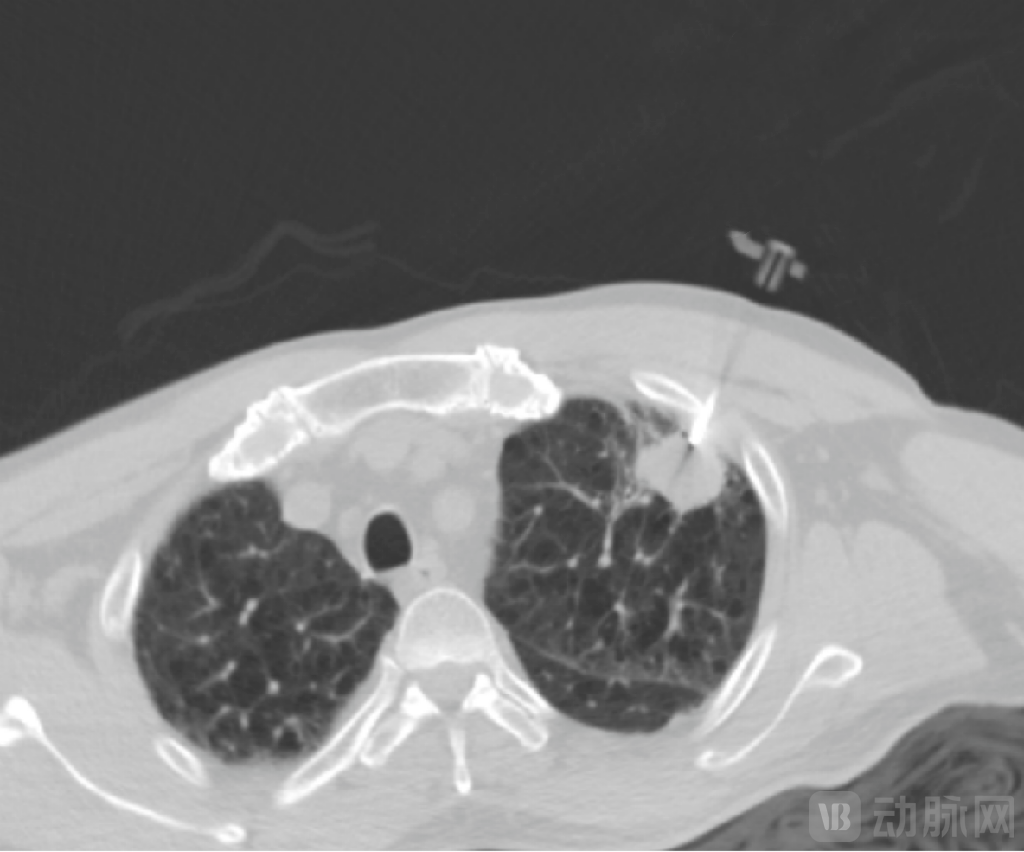

一例患者病例显示,在患者病灶粘连主动脉的情形下,MicrolGT-RoboC执行跨层穿刺规划,自动计算出进针位置及角度,精准穿到病灶。

RoboC规划执行图,图源:微引科技公众号